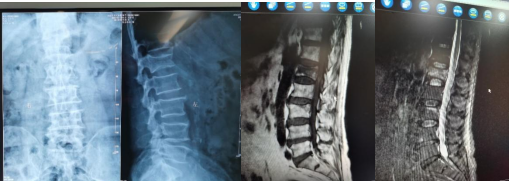

X线、MRI:腰1、3椎体压缩性骨折

完善影像学检查,经诊断明确为骨质疏松性腰1、3椎体压缩性骨折,患者腰背部疼痛剧烈伴翻身困难、无法下床活动,严重影响日常生活质量,有明确手术指征。刘博士考虑到患者高龄,且合并脑梗塞和冠心病等多种内科疾病,经过与医疗团队沟通和讨论后,决定采用经皮椎体成形术(PVP)对患者进行治疗。